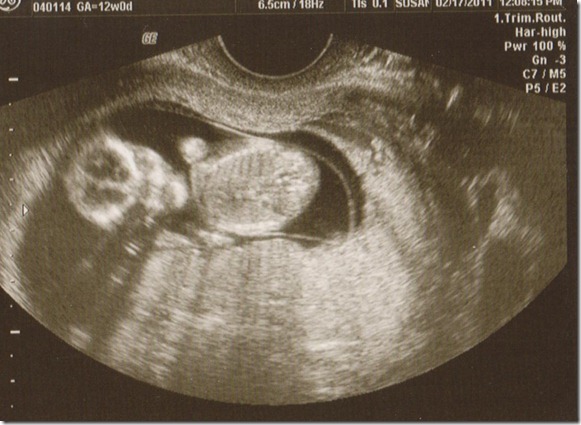

The last time that we had an ultrasound the doctors saw a little something that was cause for concern. So they suggested that we do the 1st trimester screening at 12 weeks. We had refused this screening in the past. But with a concern for a problem we would rather know about it ahead of time.

Praise God that everything was completely normal this time! We are so relieved and thankful. For those of you who have known about our concern, thank you so much for your faithful prayers. We have to believe that it was the prayers that healed our little one.

Baby playing with the cord. Look at the details of the little hand. So sweet!

Josh has been calling this baby a girl. And although we still don’t know yet, he has changed his mind because of this ultrasound shot. “I don’t know this looks just like Caleb, I think it’s a boy now”. That long back, tiny little rump and skinny legs are just like Caleb’s!